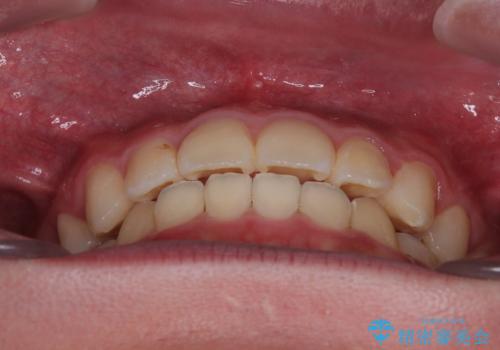

- 前歯のデコボコと口元の突出感を気にして来院された患者様です。

上下前歯がくちばしのように突出していたため、上下左右の第一小臼歯4本を抜歯し、ワイヤー装置にて矯正治療を行うこととしました。